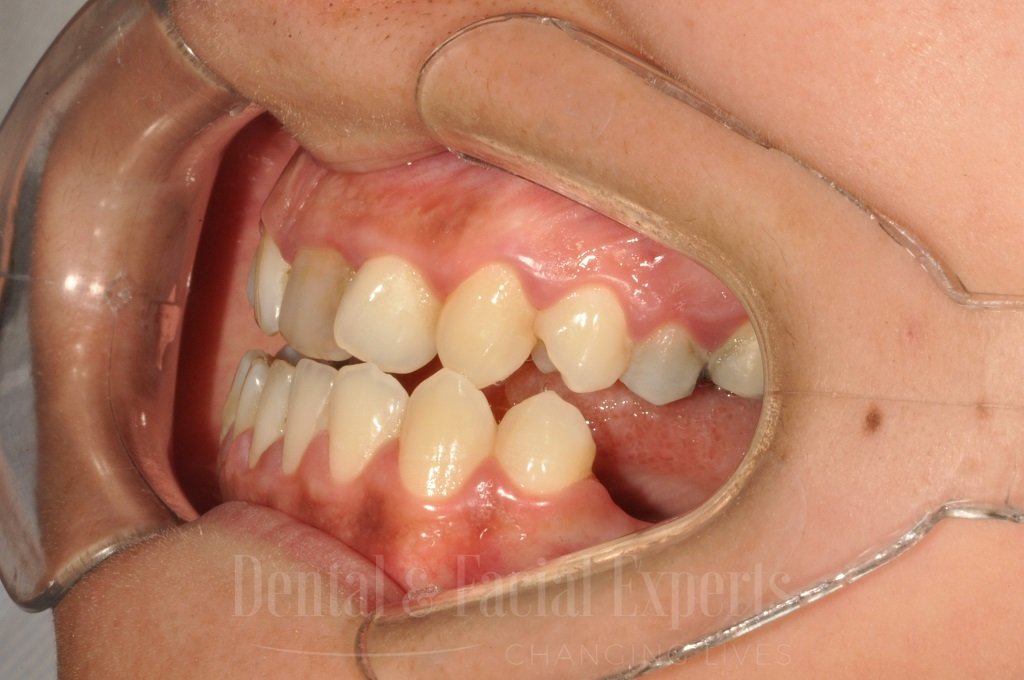

La cirugía maxilofacial es una especialidad médico-quirúrgica que aborda patologías, malformaciones y traumatismos de la cara, mandíbula, maxilares, boca y cuello. Su objetivo es restaurar la funcionalidad y mejorar la estética facial, abarcando procedimientos tanto reconstructivos como cosméticos.